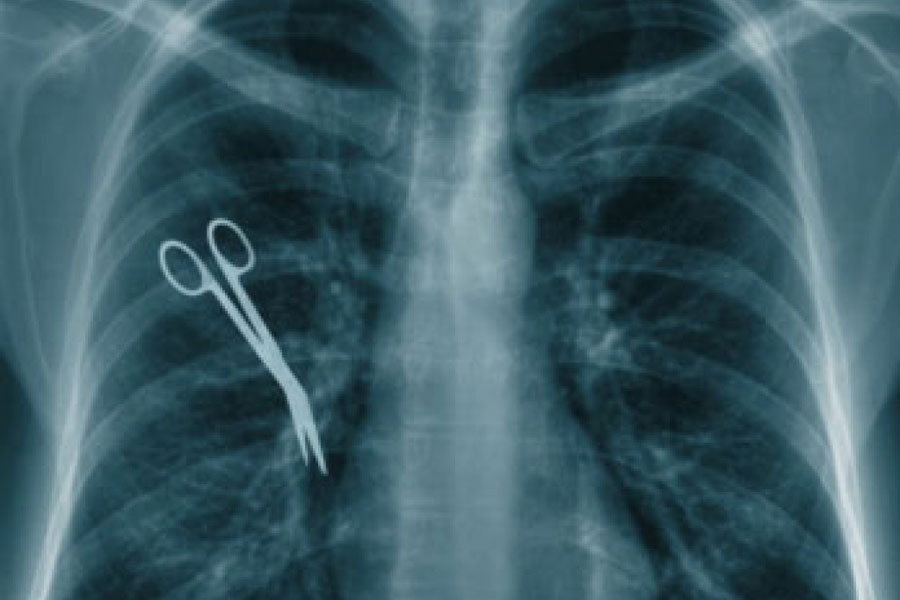

Catania, casalinga muore per setticemia: aperta un’inchiesta

Catania, una casalinga di 51 anni muore per setticemia dopo un intervento al rene per la rimozione di un calcolo e adesso, per la scomparsa della donna, sposata e ma...